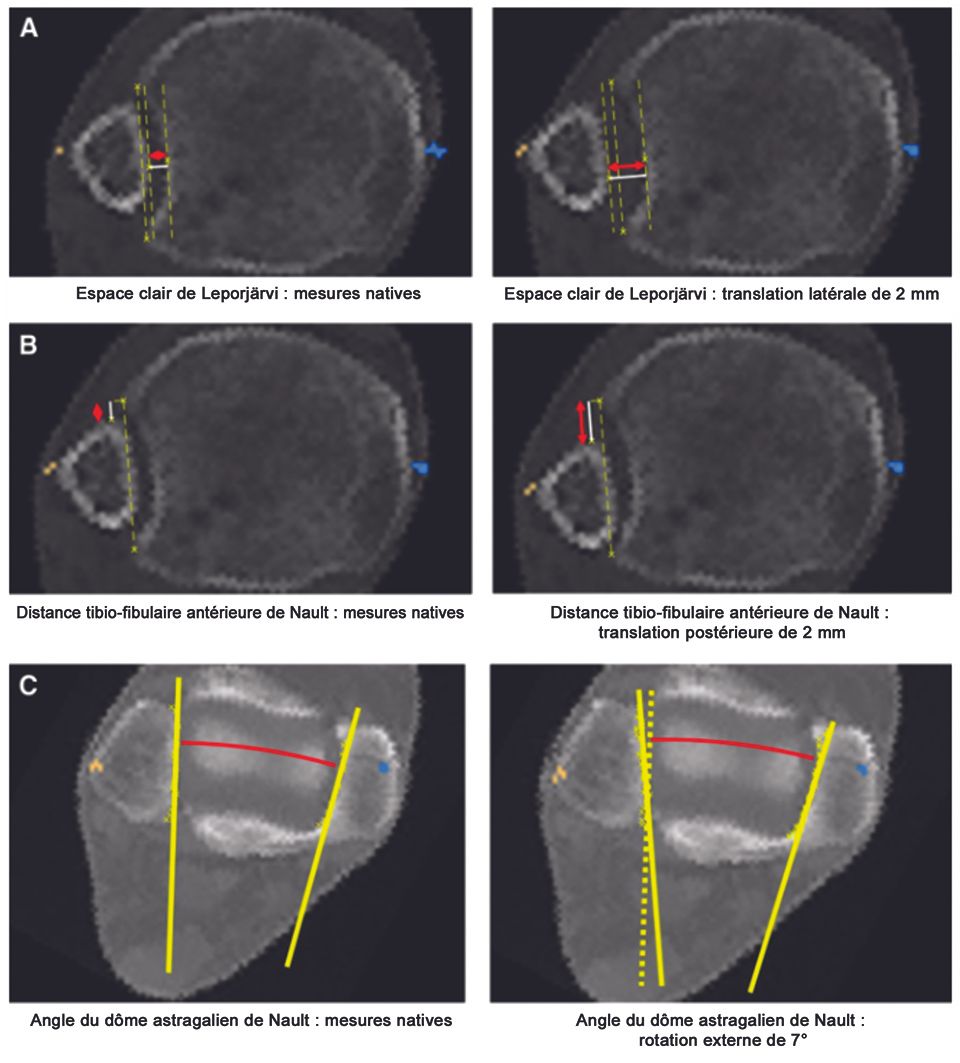

Computertomography (Figure 10)

CT scanning is an accurate method of detecting syndesmotic injuries. CT scanning of both ankles allows determination of fibular shift, rotation, shortening and the exact location of bony avulsions. Care is taken to evaluate the fibular rotation and tibiofibular distance in the horizontal plane at exactly the same level as on the uninjured side. Coronal reconstruction allows exact determination of a lateral shift of the talus and measuring of the fibular length. Generally, side-to-side differences of more than 2 mm are considered pathologic. In a recent study the three most responsive CT measurements for detecting isolated syndesmotic malreduction were described. [28] The clear space for lateral translation (Leporjärvi), the anterior tibiofibular distance for posterior translation as well as the talar dome angle for external rotation of the fibula (Nault). In diagnostic meta-analysis, the pooled sensitivity and specificity were 0.67 and 0.87 for CT respectively.[27]